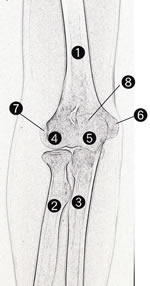

5・16・1 肘関節正面撮影

5・16・1 肘関節正面像